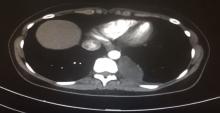

This video demonstrates a uniportal VATS surgery for the excision of a 5 x 12 cm posterior mediastinal ganglioneuroma mass.